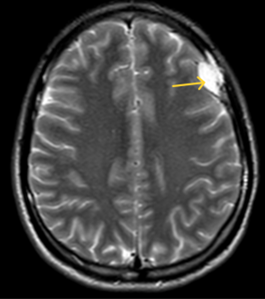

- Chụp MRI sọ não sau tiêm thuốc đối quang từ: Nằm ngoài trục vùng trán trái có nốt tăng tín hiệu trên T2W, giảm tín hiệu trên T1W, không hạn chế khuếch tán trên DWI/ADC kích thước 20x9mm, sau tiêm ngấm thuốc không đồng nhất, có dấu hiệu đuôi màng cứng, xâm lấn xương trán trái lân cận.

Hình 5: Hình ảnh MRI sọ não nốt tăng tín hiệu trên T2W, giảm tín hiệu trên T1W, xâm lấn xương trán trái (mũi tên vàng)